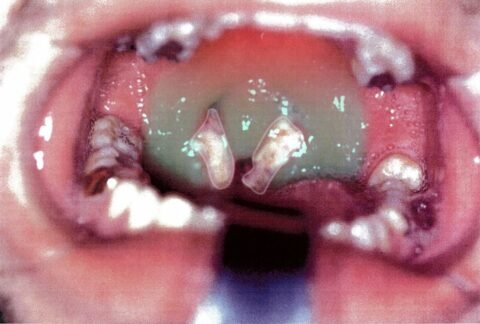

Disease Mononucleosis (Mono): Causes, Symptoms, Diagnosis & Recovery Tips ⚠️ Disclaimer: The information provided in this article is for educational purposes only and does not constitute medical advice. RevisionTown does not provide diagnosis, treatment, or medical recommendations. Always consultAdmin5 months ago5 months agoKeep Reading